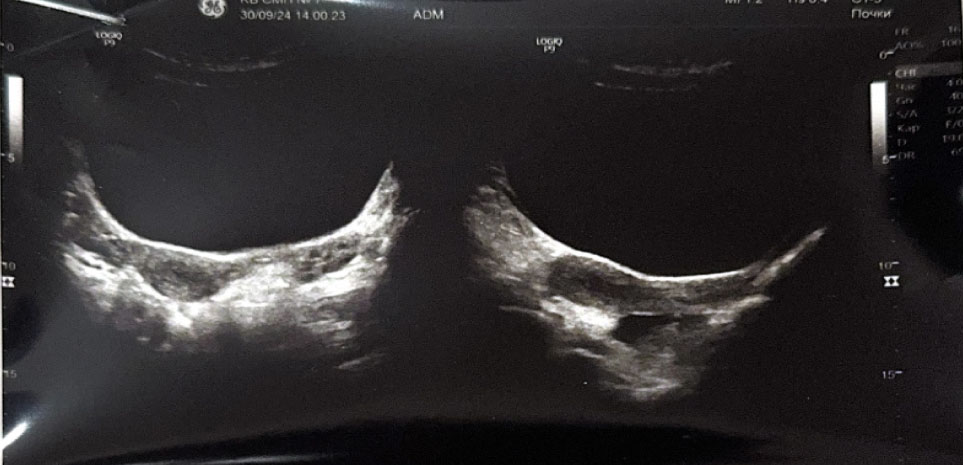

На 6-е сутки послеоперационного периода выполнено УЗИ органов малого таза: тело матки 39 × 23 × 34 мм, незначительно смещено вправо, миометрий однородной структуры. Толщина эндометрия 4 мм, соответствует фазе пролиферации. Яичники нормальных размеров, структура с фолликулярным аппаратом, соответствующим возрастной норме. Заключение: структурные изменения не выявлены (рис. 6).

Рис. 6. Ультразвуковое исследование. 6-е сутки послеоперационного периода